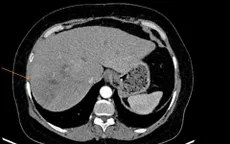

VTV.vn - Thói quen ăn gỏi cá, rau sống khiến anh L.T.N., nhiễm sán lá gan lớn, dẫn đến nhiều ổ tổn thương khu trú ở gan phải.

Bệnh nhân thủng đại tràng, tổn thương gan do sán lá gan

VTV.vn - Một tháng trước khi nhập viện, bệnh nhân T.B, 60 tuổi, trú tại Hà Tĩnh đau âm ỉ vùng thượng vị và hạ sườn phải, người mệt mỏi, chán ăn, sụt cân (5 - 6kg/tháng).